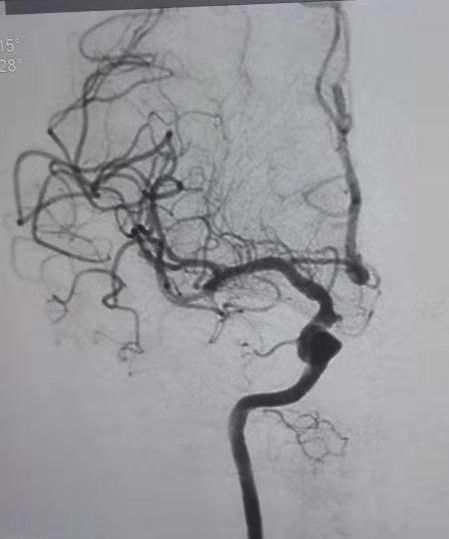

(8) 2019年1月16日开展第一例脑血管腔内取栓术。

患者:申某  男性 77岁 白寨镇

图片

术前

术后